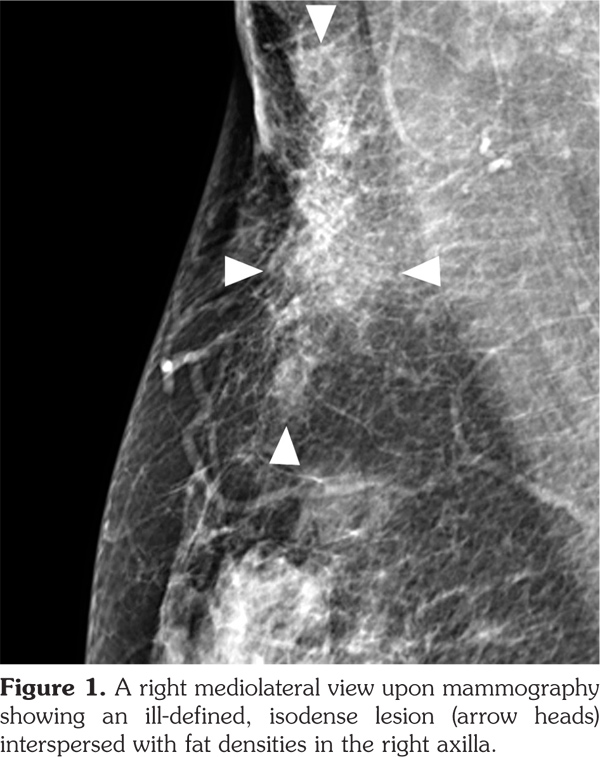

Full-field digital mammography was performed (MAMMOMAT Inspiration; Siemens AG, Munich, Germany). A right mediolateral oblique view revealed an asymmetric density in the right axilla (Figure 1). Ultrasonography was performed with a 5- to 12-MHz linear transducer (iU22; Philips Medical Systems, Bothell, WA, USA), which identified a poorly defined, elongated, homogeneously hyperechoic lesion in the subcutaneous fat layer of the right axilla (Figure 2). The lesion did not exhibit increased vascularity, except for a normal traversing venous structure (Figure 2). The lesion was surgically excised. Pathological examination confirmed the diagnosis as lipogranuloma (Figure 3). On the other hand, complete blood test results were normal.

Besides the breast and axilla, the ultrasonographic features of lipogranuloma have been described in the penis and scrotum, and have included cases with an ill-defined area of increased echogenicity in the subcutaneous tissue of the penile shaft,(11) a poorly defined extratesticular echogenic mass with an elongated appearance on a longitudinal scan,1 and an intratesticular heterogeneously hypoechoic mass.(12)